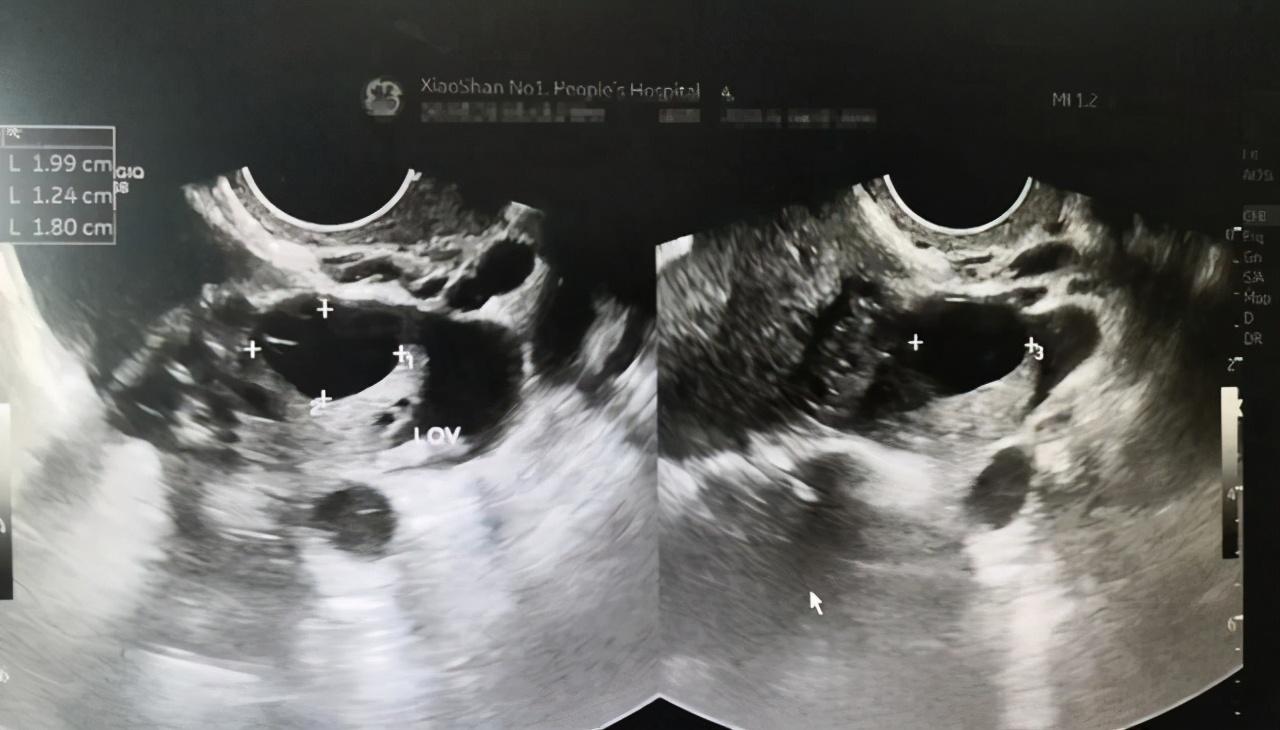

25岁的小芳在晨跑时突然感到下腹部一阵剧痛,被紧急送往医院。经过检查,她被诊断为卵巢黄体破裂。医生告诉她,这是一种常见的妇科急腹症,多发生在排卵后的黄体期。虽然多数情况下可以自行愈合,但如果出血严重,可能会导致严重的腹腔内出血,甚至危及生命。

黄体破裂是指位于卵巢表面的黄体因各种原因导致血管破裂,黄体内压力增大而引起的破裂和出血。 它好发于14-30岁的年轻女性,尤其是那些处于生育年龄、卵巢功能旺盛的女性。一项病例系列研究显示,黄体破裂患者的平均年龄为27岁。